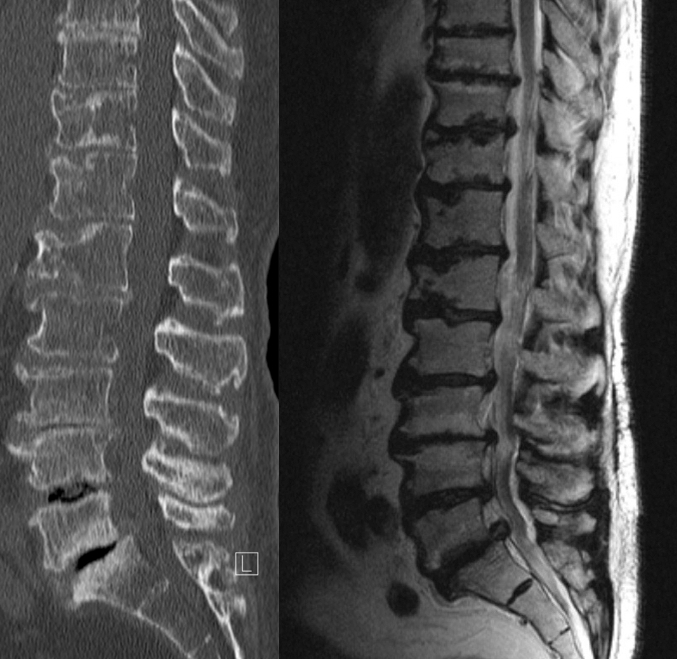

Volkskrankheit Rückenschmerzen Der Verschleiß der Wirbelsäule, der auch als Degeneration bezeichnet wird, nimmt individuell unterschiedlich mit voranschreitendem Lebensalter zu Dies hängt einerseits von äußeren Faktoren ab, zum Beispiel jahrelanger schwerer körperlicher Tätigkeit, kann aber auch genetisch. Besonderheiten der Brustwirbelsäule Der Unterschied zu anderen Segmenten der Wirbelsäule (HWS und LWS) liegt in der speziellen AnatomieSo nimmt die Größe der Bandscheiben von oben nach unten zu Im Bereich der Halswirbelsäule sind die Bandscheiben ca 3 mm dick, in der Brustwirbelsäule 5 mm und in der Lendenwirbelsäule etwa 7 mm Der Wirbelkanal ist im Bereich der Brustwirbelsäule. Degenerative Veränderung lassen sich meist von inflammatorischen, traumatischen und neoplastischen Prozessen abgrenzen Problematisch ist weiterhin die oft fehlende Korrelation von Befunden im CT oder MRT und der klinischen Symptomatik, weswegen die klinische Symptomatik und die entsprechenden Kenntnisse vorliegen müssen.

Was hinter der Erkrankung. Degenerative Veränderung lassen sich meist von inflammatorischen, traumatischen und neoplastischen Prozessen abgrenzen Problematisch ist weiterhin die oft fehlende Korrelation von Befunden im CT oder MRT und der klinischen Symptomatik, weswegen die klinische Symptomatik und die entsprechenden Kenntnisse vorliegen müssen. Dies ist vor allem der Fall, wenn zentrale Strukturen des Körpers betroffen sind, die im Alltag häufig beansprucht werden müssen Eine degenerative Erkrankung ist nicht reversibel Ist sie einmal aufgetreten, lässt die Veränderung sich nicht mehr rückgängig machen Der Verlauf der Erkrankung ist stark von der Lokalisation abhängig.

Eine Osteochondrose ist eine degenerative Veränderung der Wirbelsäule, also eine Verschleißerkrankung Dabei führen Fehlhaltungen zu Veränderungen des Bandscheibenknorpels sowie zu knöchernen Anbauten der Wirbelkörper In der Folge kommt es unter anderem zu Rücken und Nackenschmerzen, die vor allem in Ruhe auftreten Doch wie entsteht eine Osteochondrose?. Patienten mit degenerativen Veränderungen der Wirbelsäule können ambulant oder im Rahmen eines stationären Aufenthalts umfassend klinisch und bildgebend mit Röntgen, Computertomographie (CT) sowie Magnetresonanztomographie (MRT) untersucht und im Rahmen unserer fachübergreifenden multimodalen Schmerztherapie konservativ funktionell behandelt werden. Auftretende degenerative Veränderungen der lumbalen degenerative irreversibel Die Behandlung besteht in der Regel aus Linderung von Schmerzen, Entzündungen, Beseitigung und Verhinderung der Verschlechterung Diagnostik Finding Symptome der Wirbelsäule Pathologie, muss der Patient zunächst Hilfe von einem Neurologen suchen.